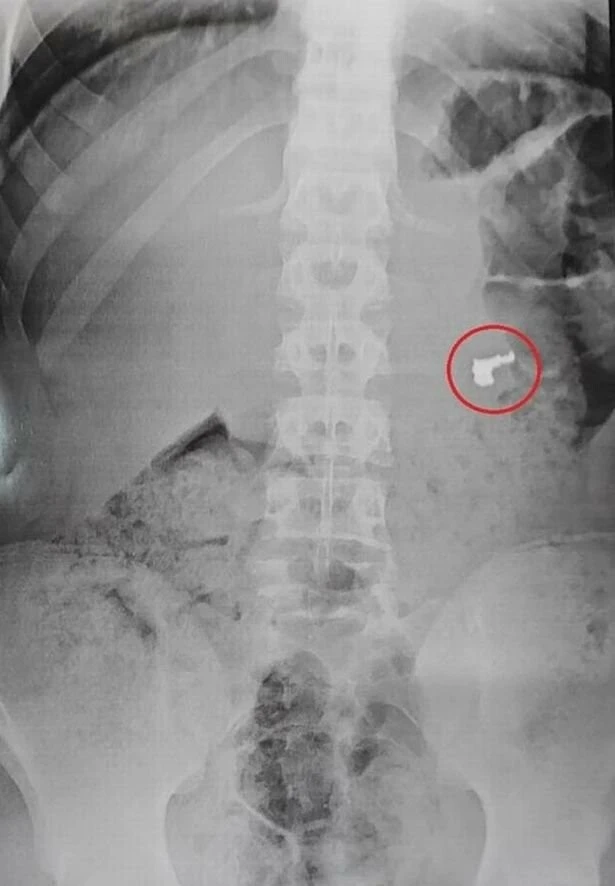

Polisler, hırsızları yolda durdurdular, üzerlerini aradılar fakat bir şey bulamadılar. Daily Star'ın haberine göre, polisler işkillendikleri hırsızları, kontrol amaçlı sağlık kuruluşuna götürdüler. Röntgen esnasında ise şaşırtıcı durum gözler önüne serildi.

Zanlılardan birinin midesinde altın bir zincir bulundu. Gencin yaptığı hırsızlığın ardından yakalanmamak için kolyeyi yutması ise hastanedekiler tarafından şaşkınlıkla karşılandı.